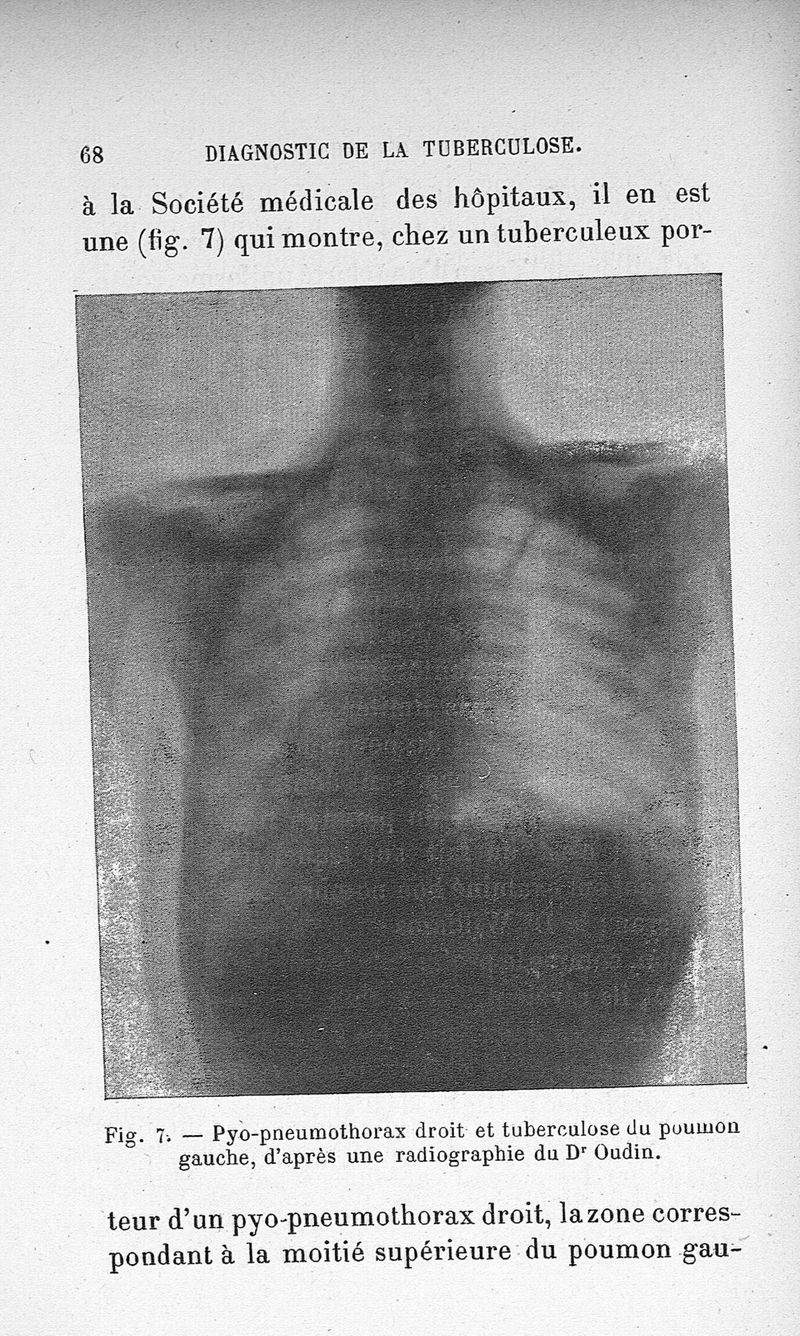

Les rayons de Röntgen et le diagnostic de la tuberculose